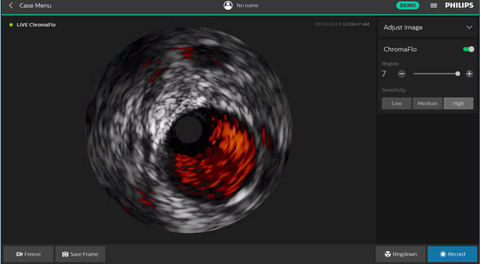

ChromaFlo обеспечивает простую оценку аппозиции стента, размера просвета сосуда и других параметров за счет выделения кровотока красным цветом на изображении в одно нажатие кнопки. Функция ChromaFlo доступна на системах для интервенционных вмешательств Philips.

Эта функция создана для быстрой оценки размера просвета сосуда и аппозиции стента; она облегчает определение ветвей сосудов, диссекций и тромбов, а также упрощает оценку распределения бляшек в области бифуркаций. Функция ChromaFlo выделяет кровоток красным цветом, что помогает:

Во время визуализации не требуется выполнять промывание или какие-либо специальные процедуры. Просто активируйте функцию ChromaFlo одним нажатием кнопки.

Функция ChromaFlo совместима с цифровыми катетерами для ВСУЗИ Philips Eagle Eye Platinum.